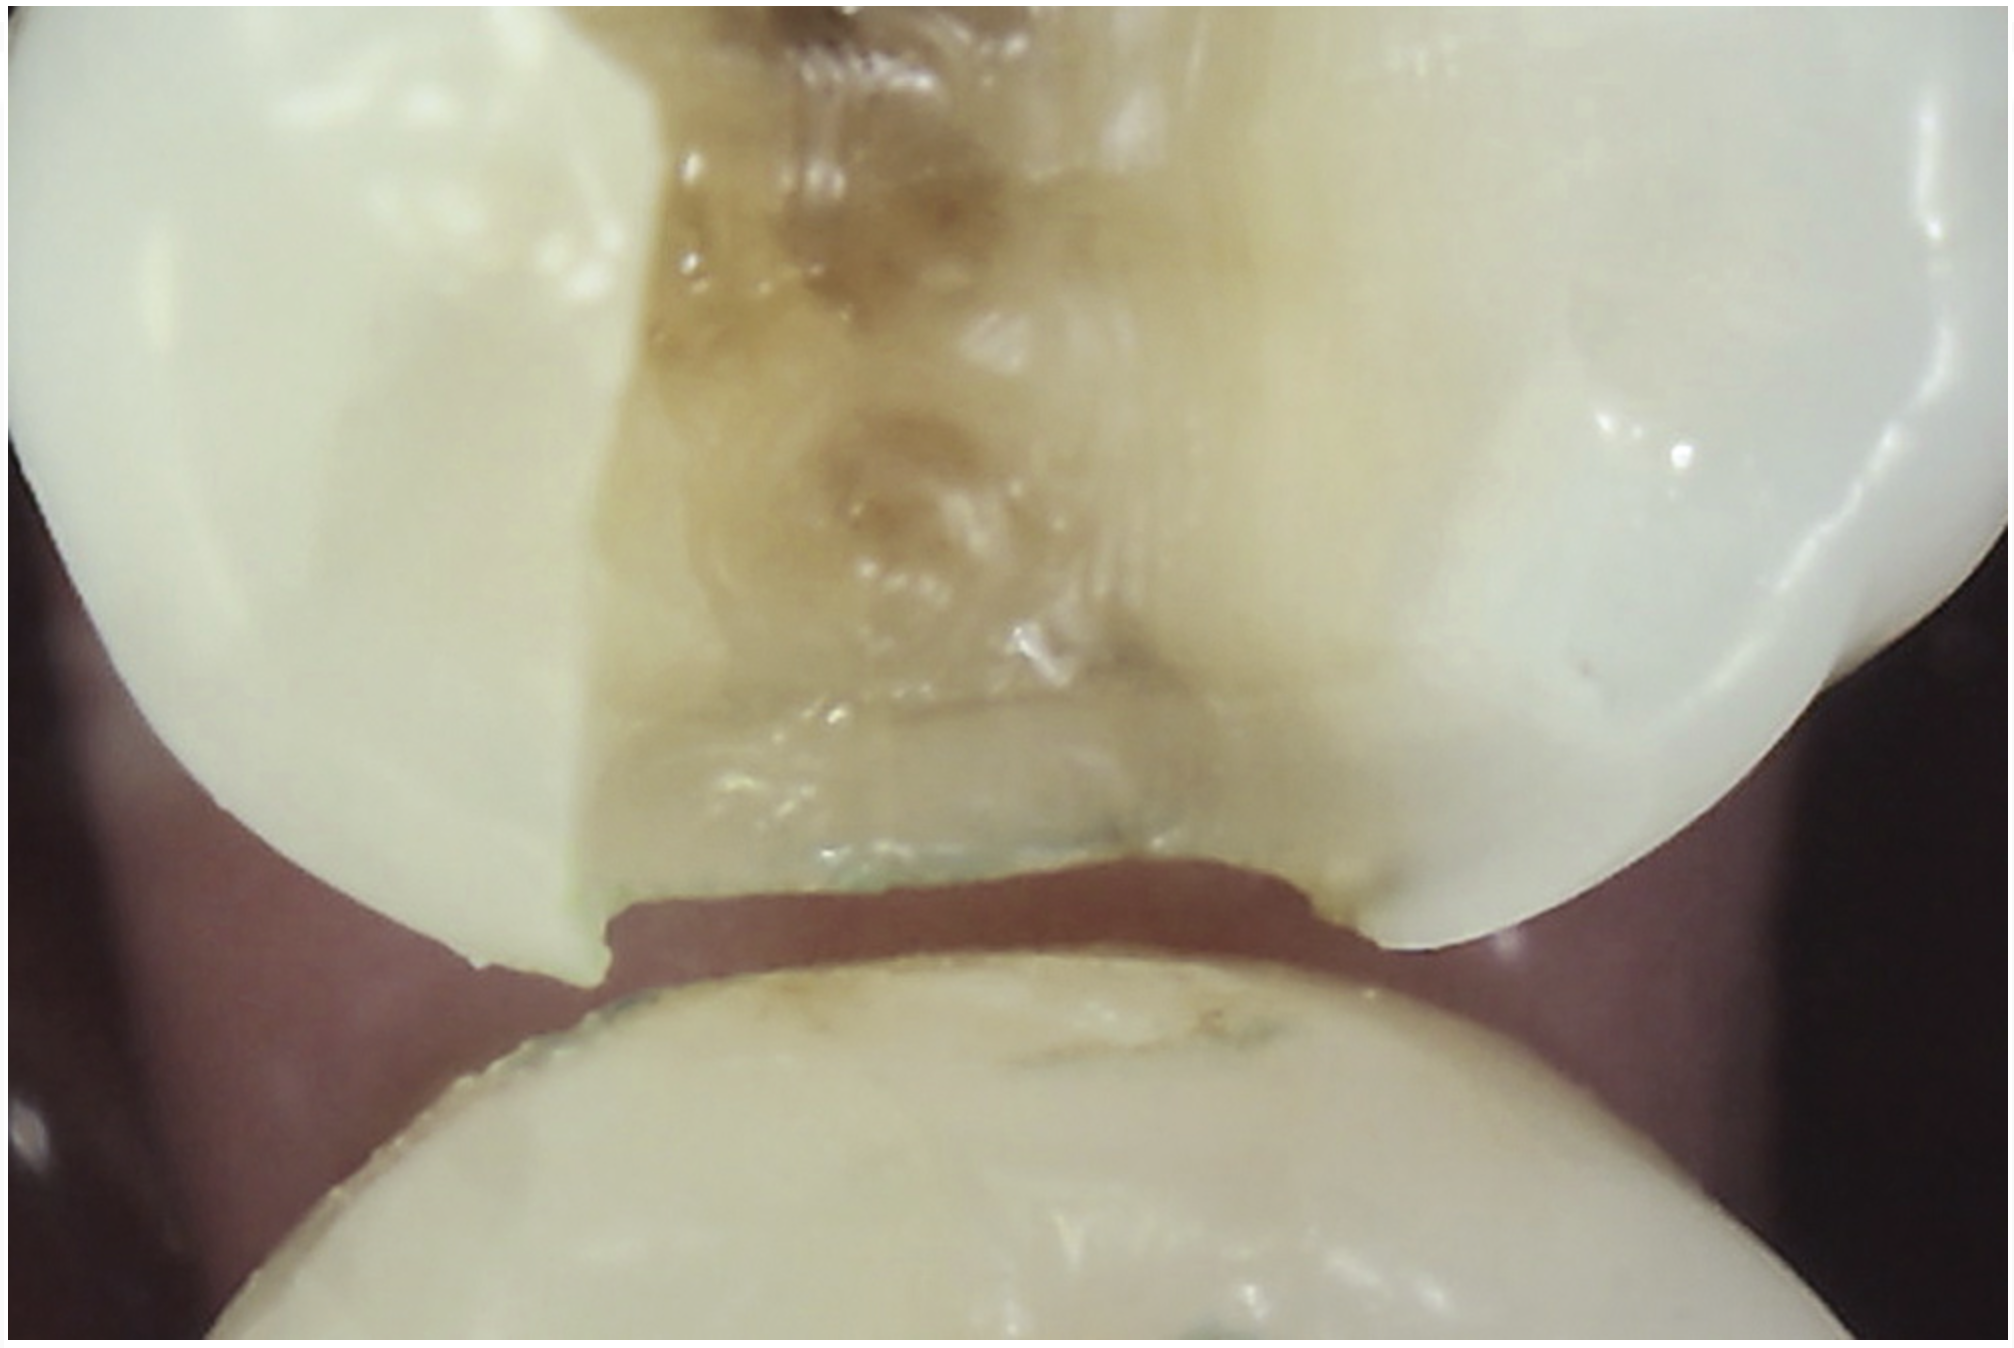

Methylene blue dye is the most commonly used dye to stain cracks because of its pooling tendency.2,3,14,16,17,23 The dye pools into the enamel and dentin cracks and the tooth is thoroughly rinsed. The resulting dark stain retained in the crack lines then helps enable cracks to be detected (Figure 4 and Figure 5). Methylene blue dye, however, also stains dental plaque, requiring the tooth surface to be cleaned with pumice or prophylaxis paste before dye application.14 The dye also can be absorbed by dentin, but any residual dye can be removed using a 10-second phosphoric acid etch.14 A comparative study of dye staining and transillumination concluded that methylene blue dye staining and transillumination performed simultaneously is the optimal crack assessment technique.23

Fig 4. Subtle asymptomatic occlusal crack (arrow) of a mandibular right second molar (occlusal view).

Figure 4

Fig 5. Methylene blue dye staining further revealing the occlusal extent of the crack shown in Fig 4.

Figure 5